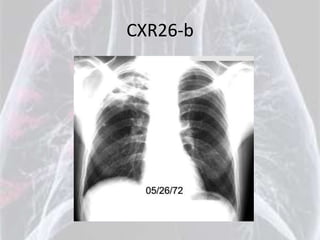

CXR26-b

Diagnosis for CXR26 is: Ankylosing Spondylitis

Bamboo spine